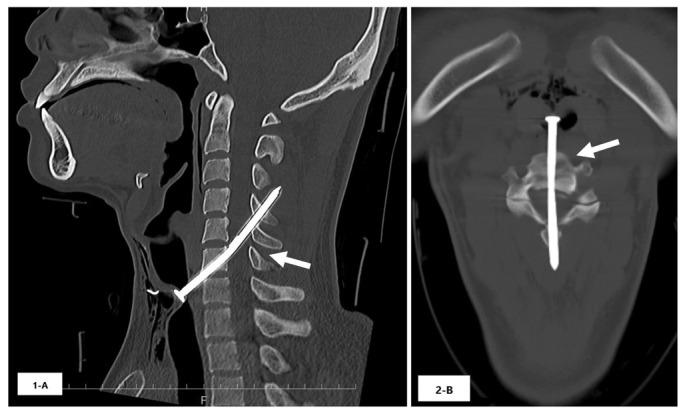

A 26-year-old man was impaled by a nail after a nail gun accident. He was fully conscious with weakness and loss of sensation in the extremities. Cervical computed tomography showed a 9-centimeter long nail penetrating the spinal cord. The nail was removed surgically six hours after the incident. Neurological deficits gradually improved, and at three-month follow-up the patient had completely recovered from muscle weakness and reported only mild sensory deficits in the bilateral sole of his foot.

This case showed a favorable neurological course, which may be attributed to the fact that the cervical spinal cord injury did not involve the corticospinal tracts and anterior horn.